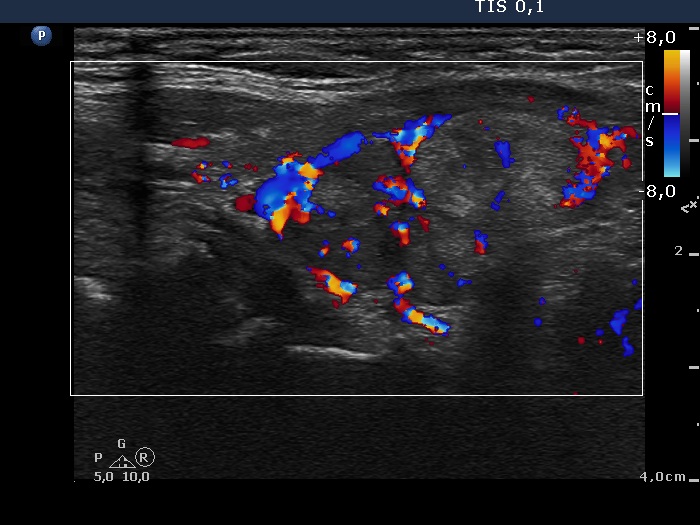

Discrete lesion or nodule in Hashimoto's thyroiditis - case 4 (104) (ultrasonographic picture 7)

Left lobe, longitudinal scan, color Doppler mode. The vascularization is not specific.